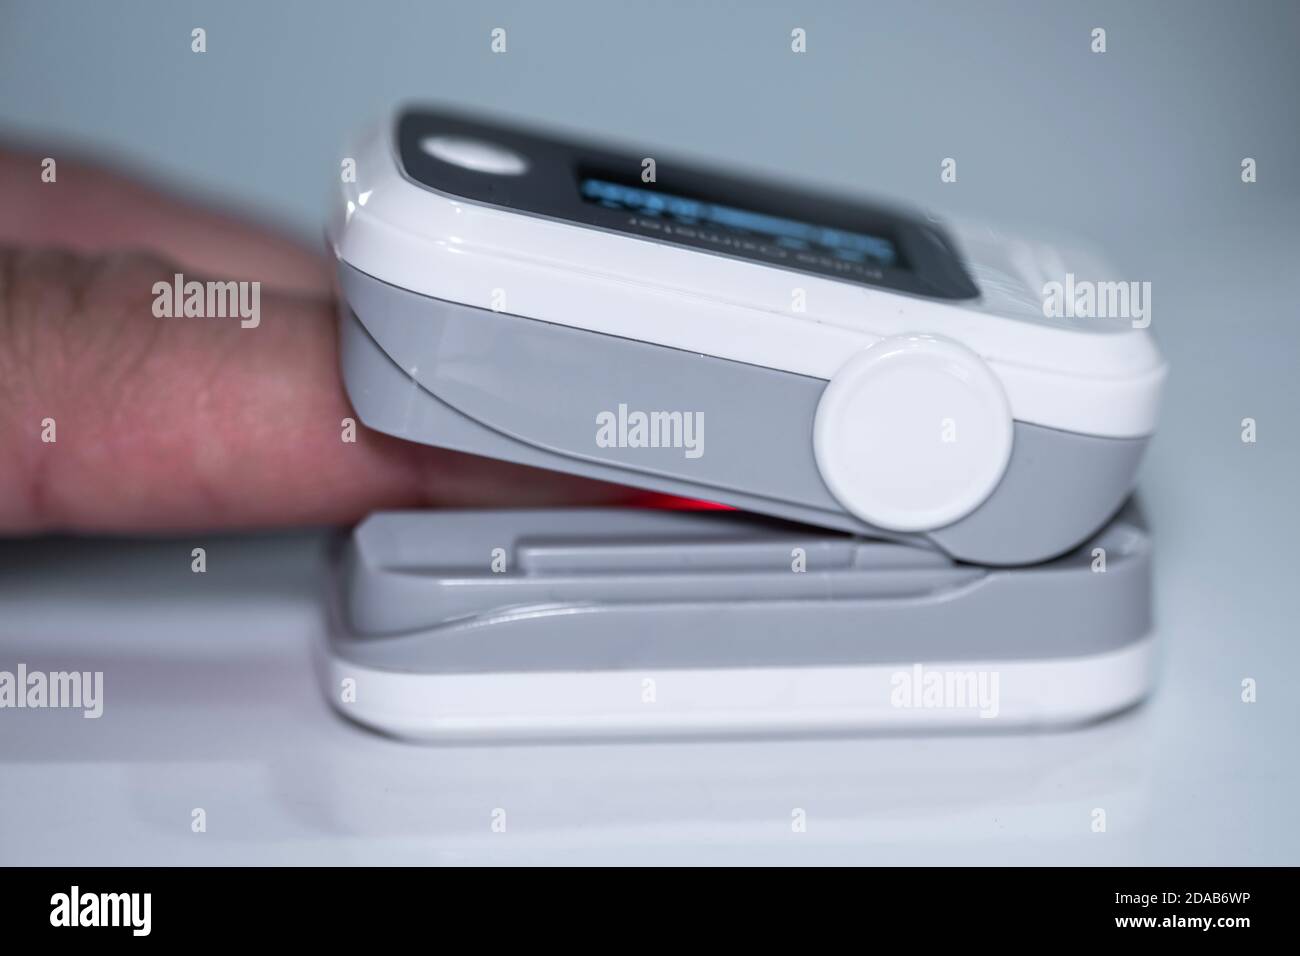

Man use pulse oximeter to measure oxygen blood saturation in covid19 pandemic disease,medical home monitoring vital signs treatment Stock Photohttps://www.alamy.com/image-license-details/?v=1https://www.alamy.com/man-use-pulse-oximeter-to-measure-oxygen-blood-saturation-in-covid19-pandemic-diseasemedical-home-monitoring-vital-signs-treatment-image385021554.html

Man use pulse oximeter to measure oxygen blood saturation in covid19 pandemic disease,medical home monitoring vital signs treatment Stock Photohttps://www.alamy.com/image-license-details/?v=1https://www.alamy.com/man-use-pulse-oximeter-to-measure-oxygen-blood-saturation-in-covid19-pandemic-diseasemedical-home-monitoring-vital-signs-treatment-image385021554.htmlRF2DAB6WP–Man use pulse oximeter to measure oxygen blood saturation in covid19 pandemic disease,medical home monitoring vital signs treatment